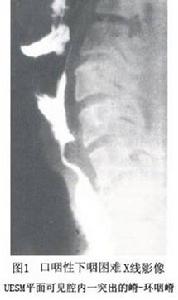

環咽肌失弛緩症1.放射線檢查對於口咽性下咽困難的病人需要進行多階段、多體位透視和電視掃描檢查。由於吞咽過程中各個環節的快速活動,只有套用這些技術才能準確的記錄,如舌的運動、軟顎的活動、咽部收縮的對稱性、喉的活動,以及原來處於靜息狀態下的UESM的活動情況等。特發性UESM功能障礙病人作食管造影時有時可見UESM平面有一向食管腔內突出的嵴(cricopharyngealbar),稱為“環咽嵴”正常人有5%有此種現象。